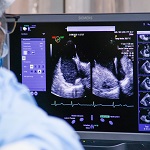

A través de un acceso venoso en la ingle, los especialistas ingresaron un catéter hasta el lado derecho del corazón. “Previamente, ya se había definido entre cuáles de los velos estaba la insuficiencia y allí instalamos los clips, que tiene dos ‘patitas’ que agarran -cada una por separado- estos velos y los sellan, dando solución al problema valvular”. Para obtener los resultados esperados, el procedimiento fue asistido mediante ecografía, a través del esófago.